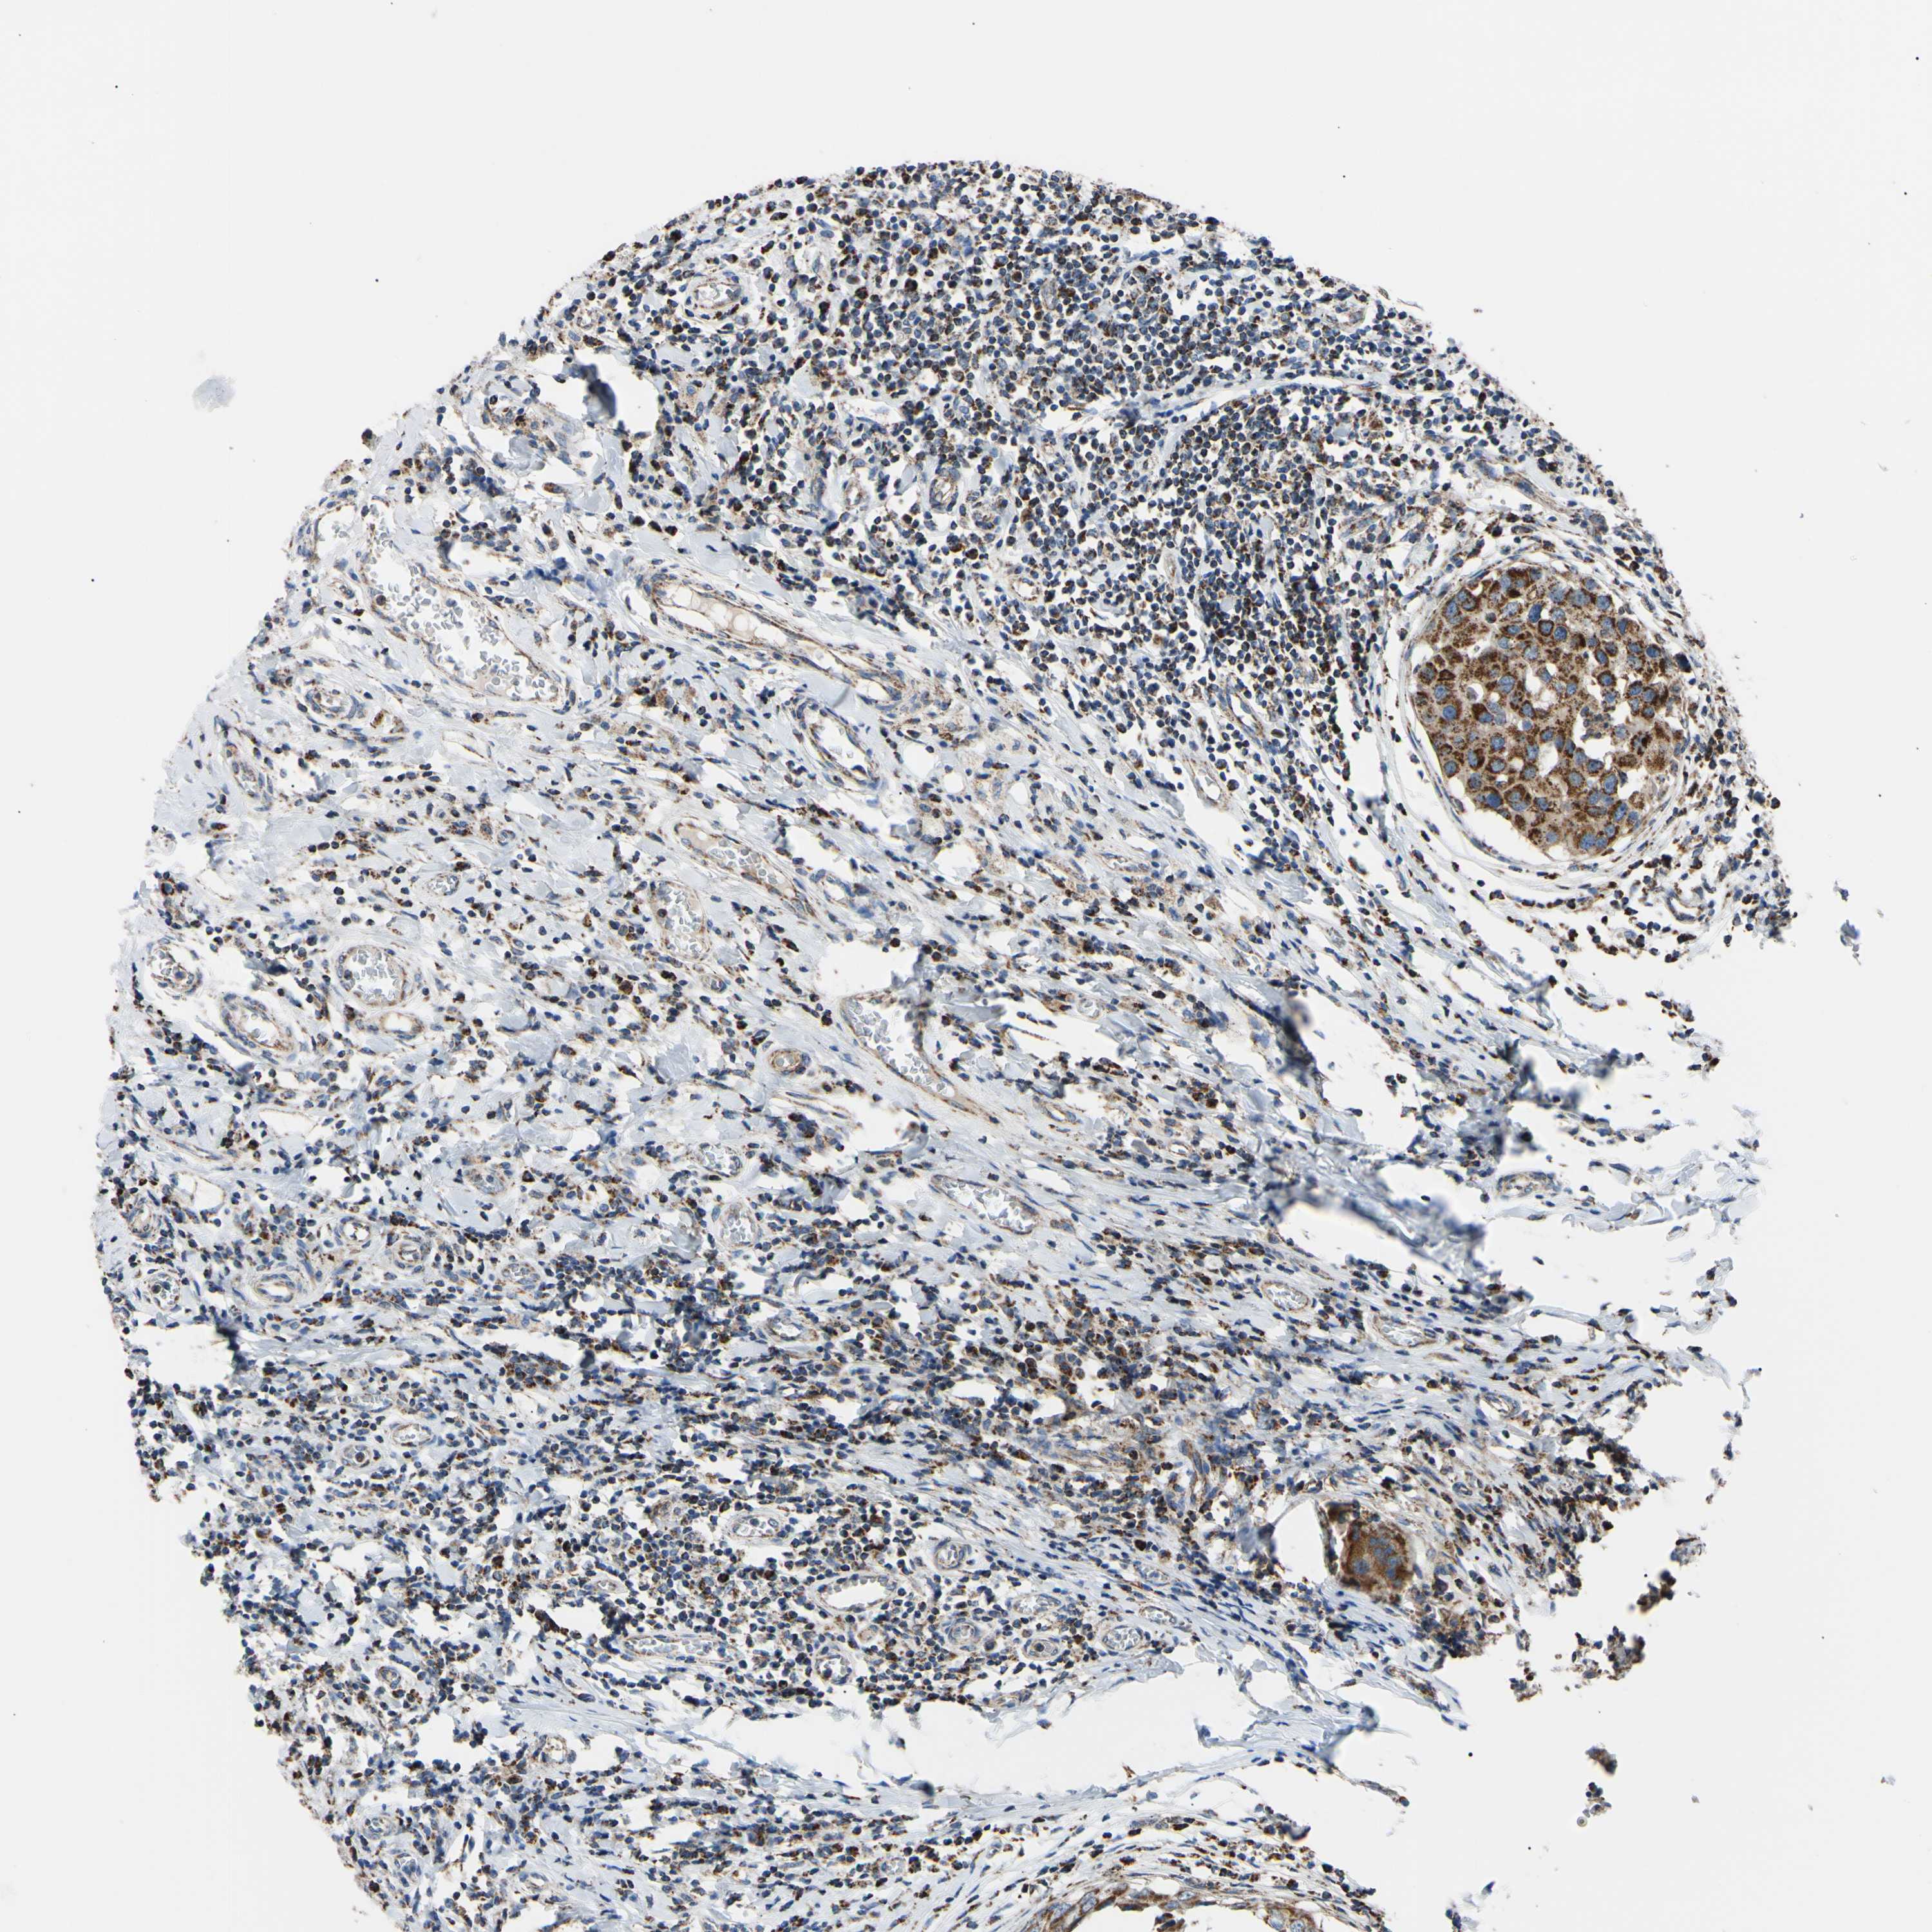

CANCER BREAST CANCER Show tissue menu

BRCA TCGA BRCA VALIDATION PROTEIN EXPRESSION